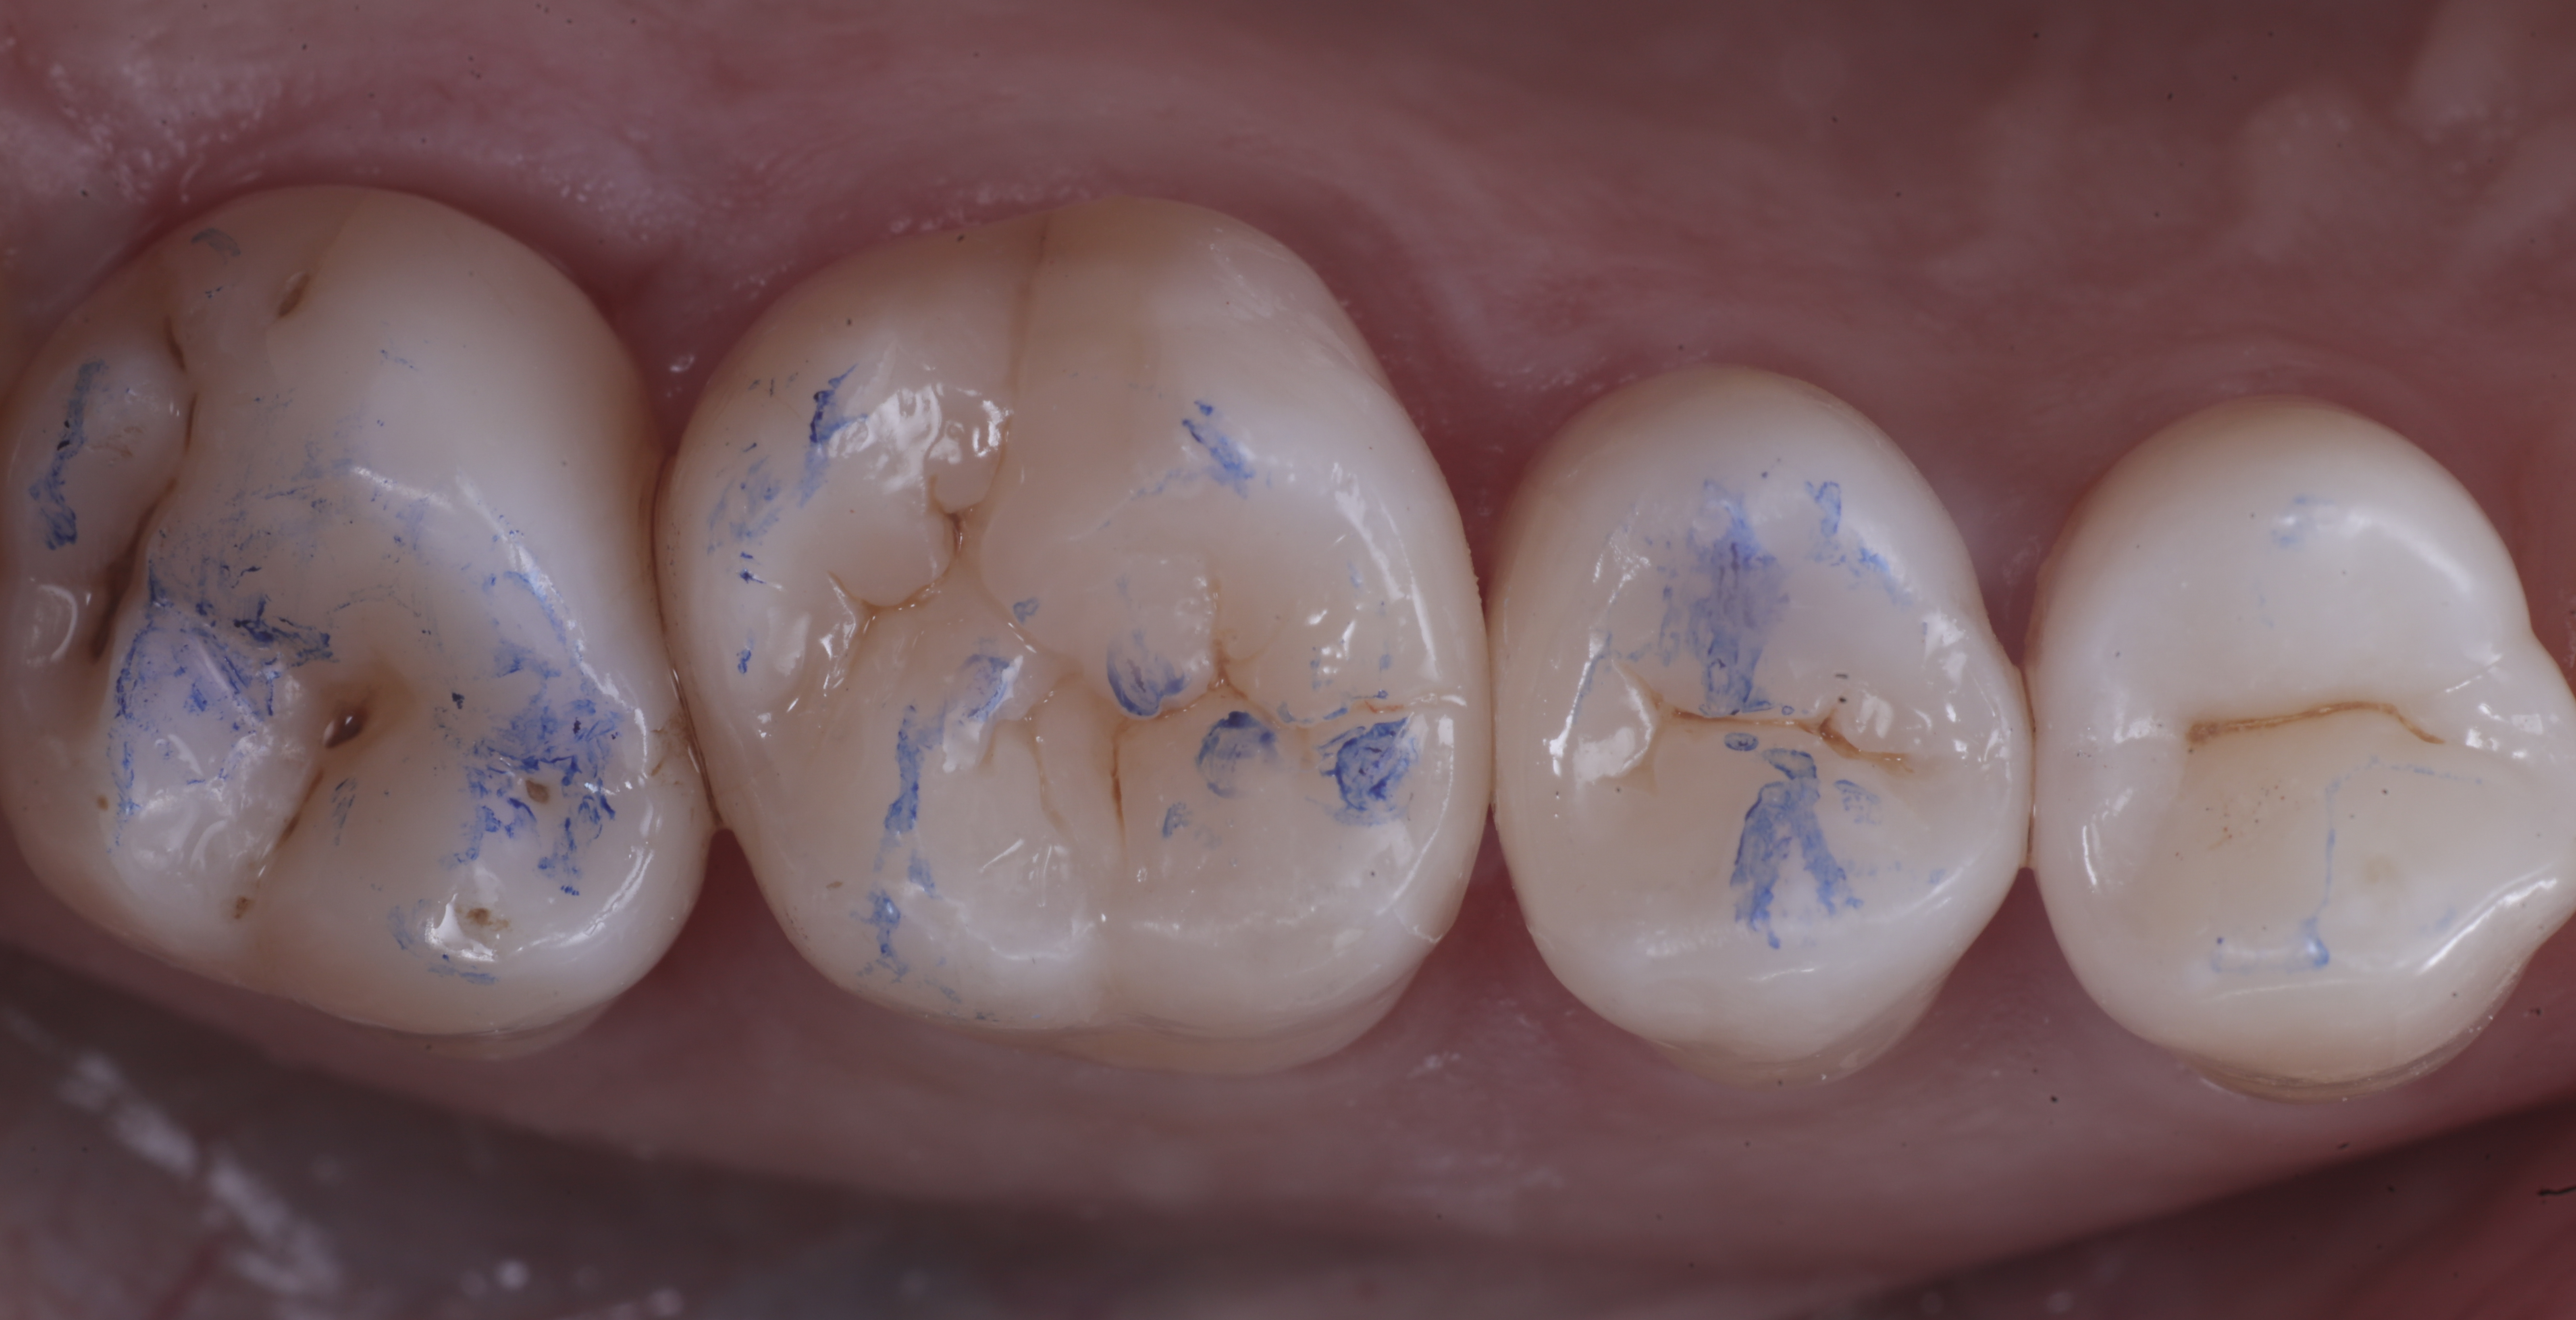

foto 8 Modellazione ed aspetto occlusale

foto 9 Modellazione ed aspetto vestibolare

foto 6 Aspetto occlusale delle pareti interprossimali appena create

foto 7 Aspetto vestibolare delle pareti interprossimali appena create